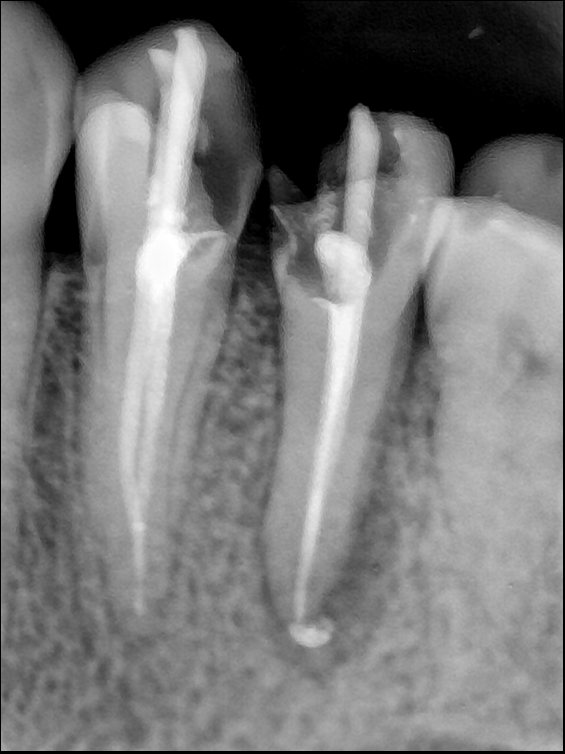

第三版算法分辨率效果比较

| 编号 | 原图 | 第一版 | 第二版 | 第三版 1216x1600 | 第三版 768x1024 | 第三版 1120x1120 |

|---|---|---|---|---|---|---|

| 131315.jpg | ![]() | ![]() | ![]() | ![]() | ![]() | ![]() |

| 131316.jpg | ![]() | ![]() | ![]() | ![]() | ![]() | ![]() |

| 131317.jpg | ![]() | ![]() | ![]() | ![]() | ![]() | ![]() |

| 131318.jpg | ![]() | ![]() | ![]() | ![]() | ![]() | ![]() |

| 131319.jpg | ![]() | ![]() | ![]() | ![]() | ![]() | ![]() |

| 131320.jpg | ![]() | ![]() | ![]() | ![]() | ![]() | ![]() |